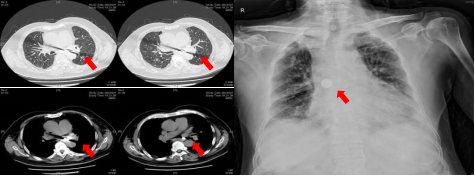

图1. 入院胸部CT示左主支气管内硬币大小异物一枚(红色箭头所示)入院第2天复查床旁胸片提示硬币样异物自行转移至右主支气管内(红色箭头所示)。

听完刘大爷的讲述,呼吸科病房李理主治医师为他安排了胸部CT,结果提示左主支气管内异物,需要通过电子支气管镜取出。当刘大爷经牟医生提示看到片子中的圆形异物时,才恍然想到,这竟是春节吃到的那枚硬币!

但由于患者肺功能较差导致血氧较低,不能承受经鼻腔的全麻支气管镜,经与麻醉科评估,牟向东为他行半麻的经口行支气管镜,镜下可见硬币已从左主支气管内滚动到右主支气管内且嵌顿管口,牟向东用异物钳快速顺利取出异物,时间不到1分钟,刘大爷气短、咳嗽症状明显缓解。